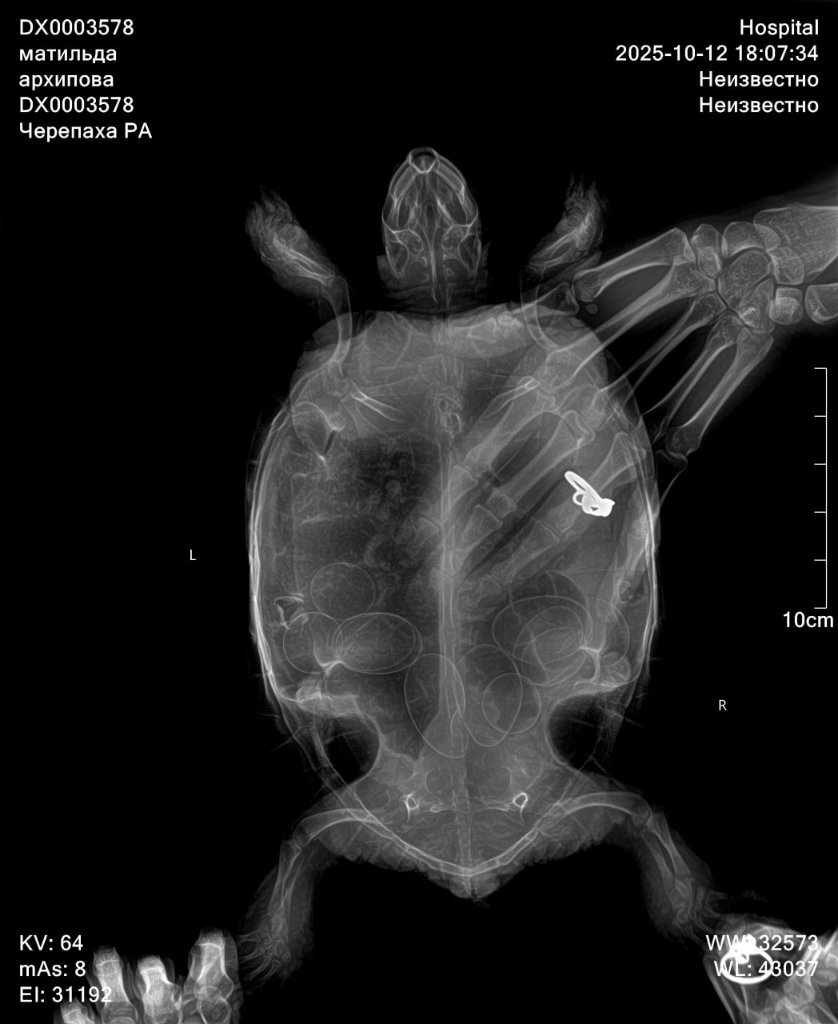

Здраствуйте, сегодня обратилась в другую клинику, прогноз не благоприятный, есть признаки почечной недостаточность, есть переизбыток бактерий в кале, есть признаки стоматита в полости рта. Все это очень и очень плохо. Сделали рентген по направлению, к сожалению описание рентгена рентгенологи сделать не могут, без дополнительной платы. Но завтра я уже записана со снимками на повторный приём. Моя огромная ошибка что ограничилась визитами к одному доктору, и потеряла очень много времени. Тк изначально состояние более стабильное хотябы визуально. Завтра получим назначения от главного врача специалиста по экзотам. Покажу им новые снимки. По фото вроде насчитала тоже количество яиц. Но они значительно сместились, вероятно из-за не к месту сделанного окситоцина